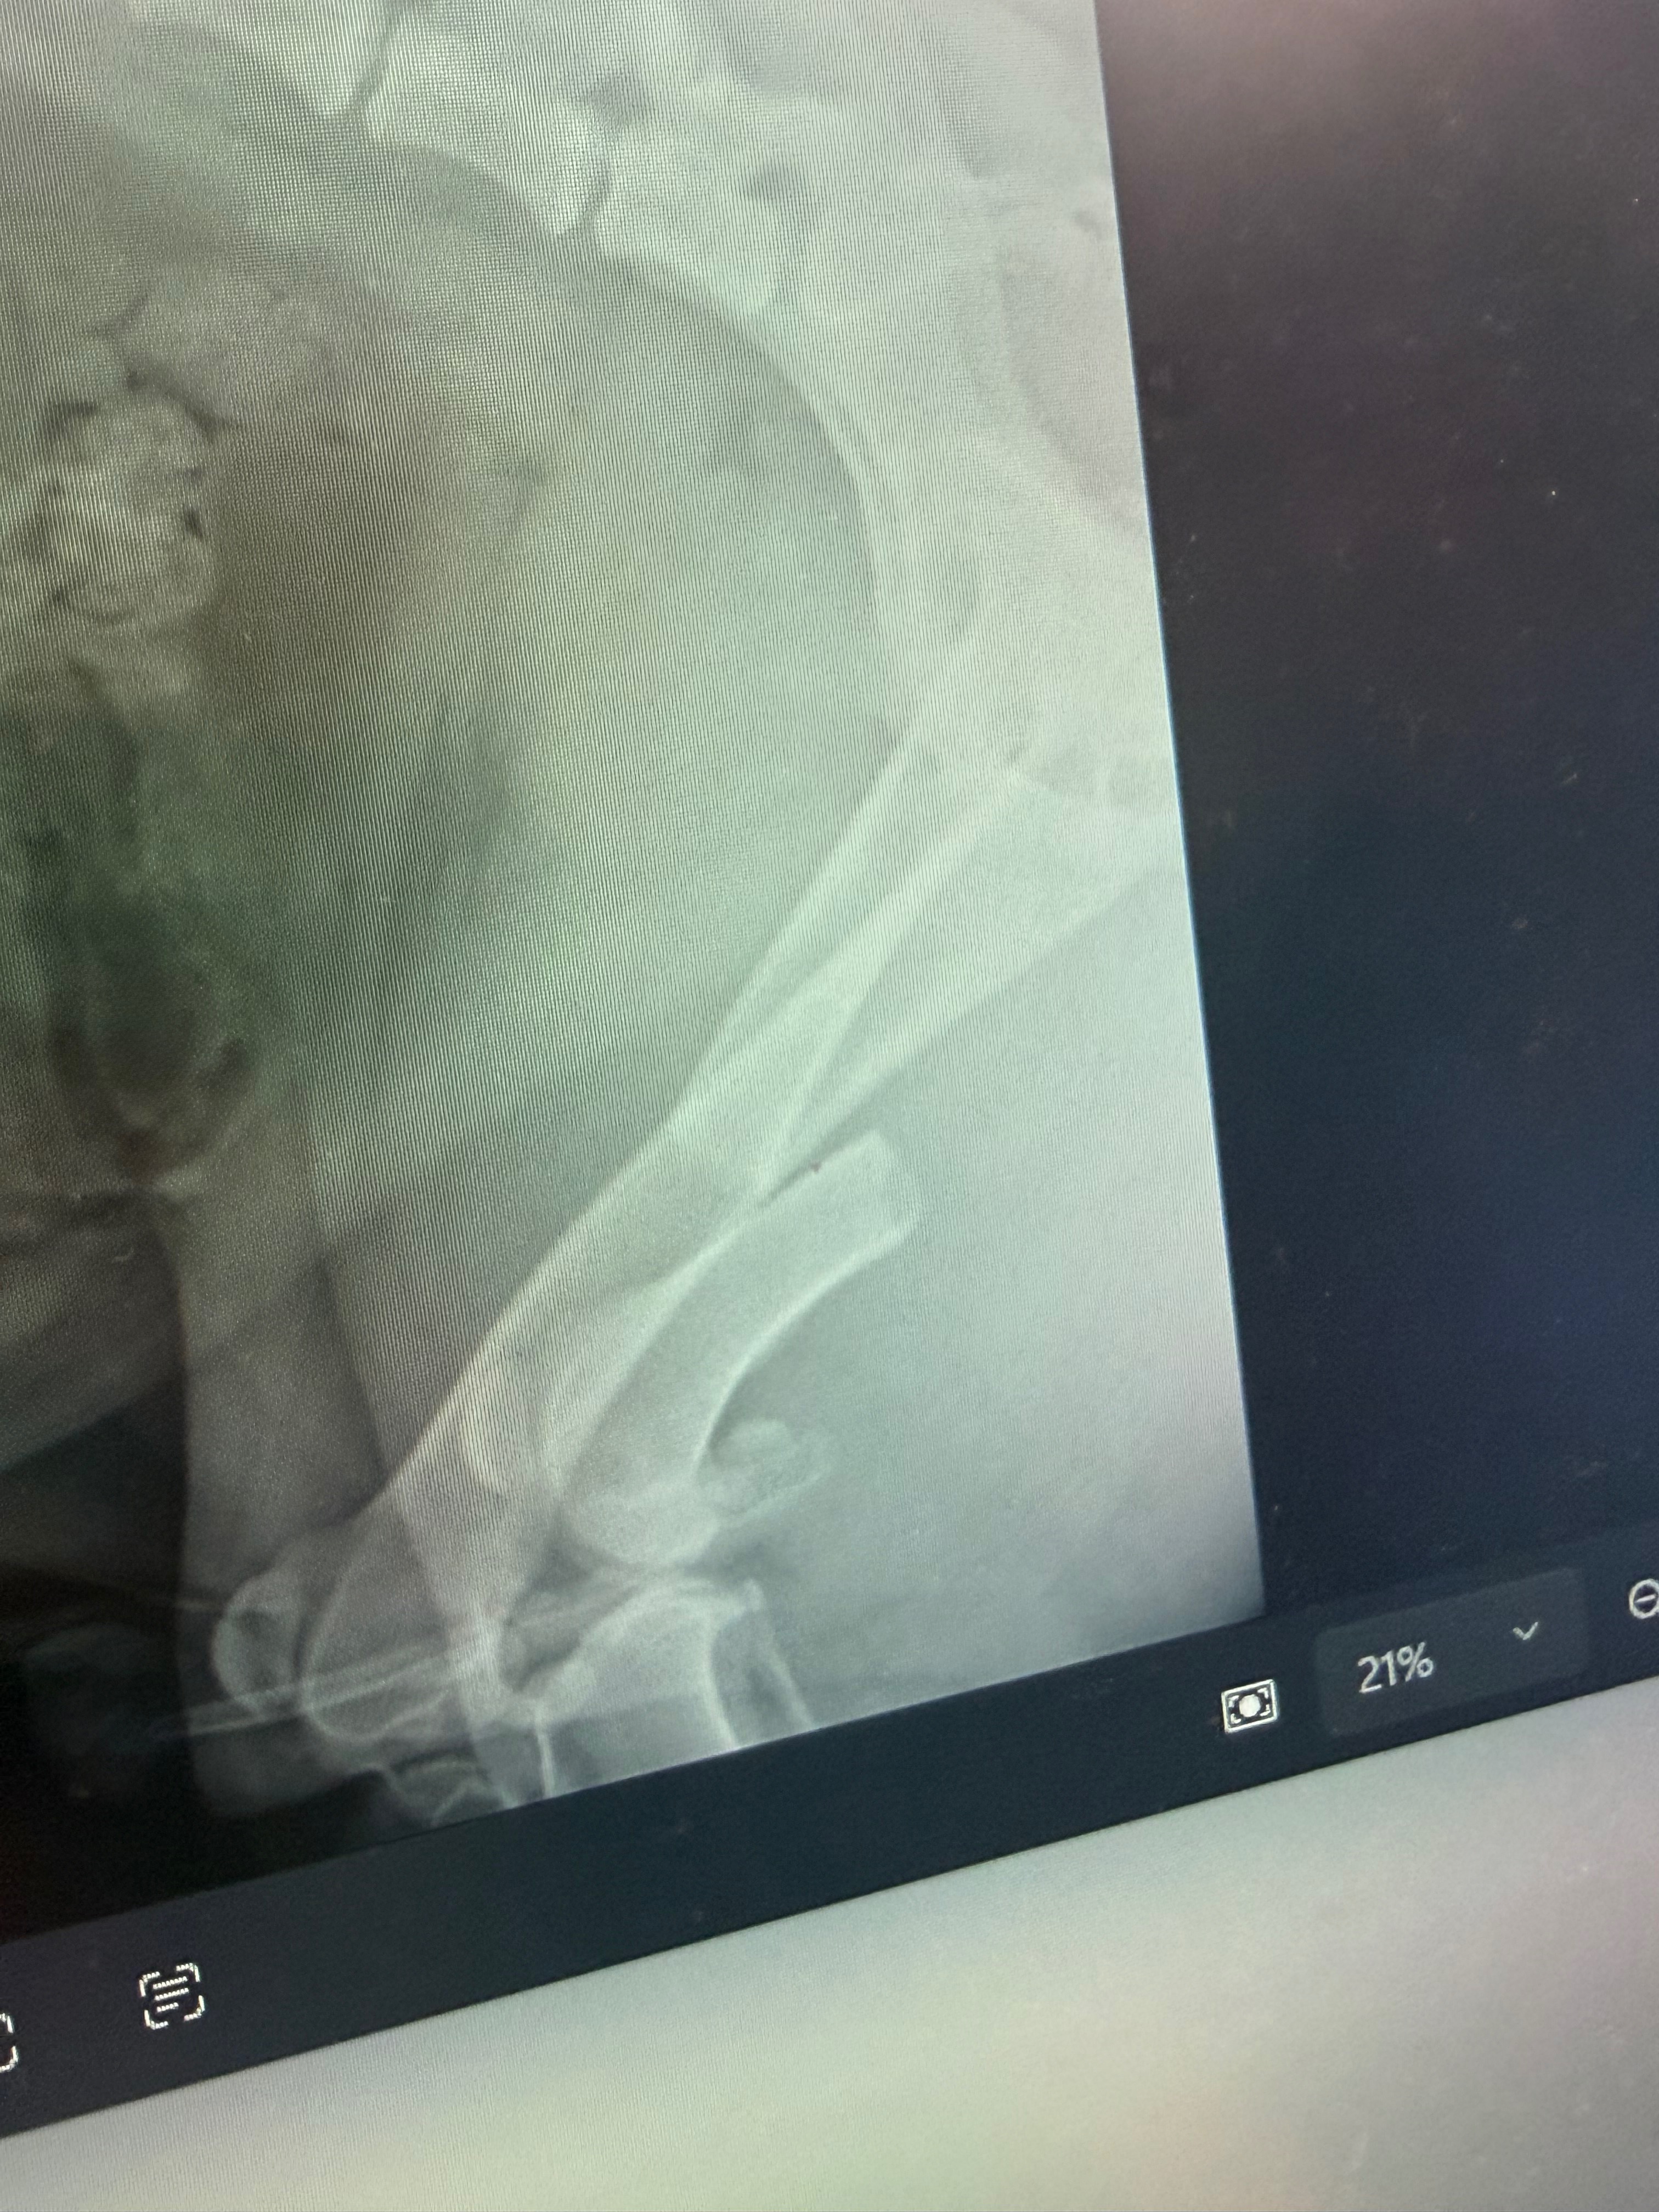

Koda suffered a broken leg, bruised lungs and heart, and several other serious injuries. He is currently on constant oxygen and receiving intensive veterinary care as doctors work tirelessly to stabilize him and give him the best chance at recovery. The road ahead will include surgery, continued hospitalization, medications, and rehabilitation.